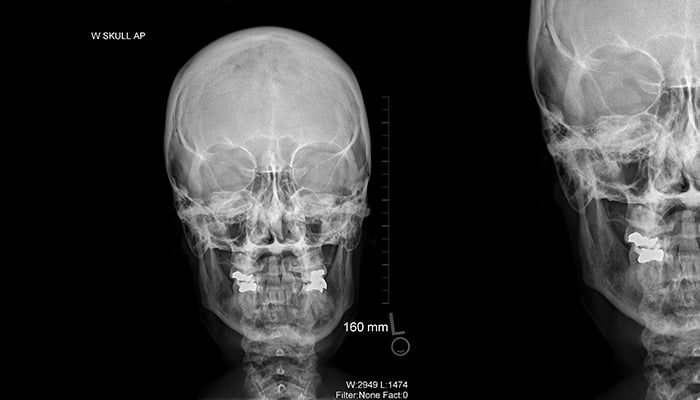

Skull X-ray

X-ray of a skull

Image © ASRT